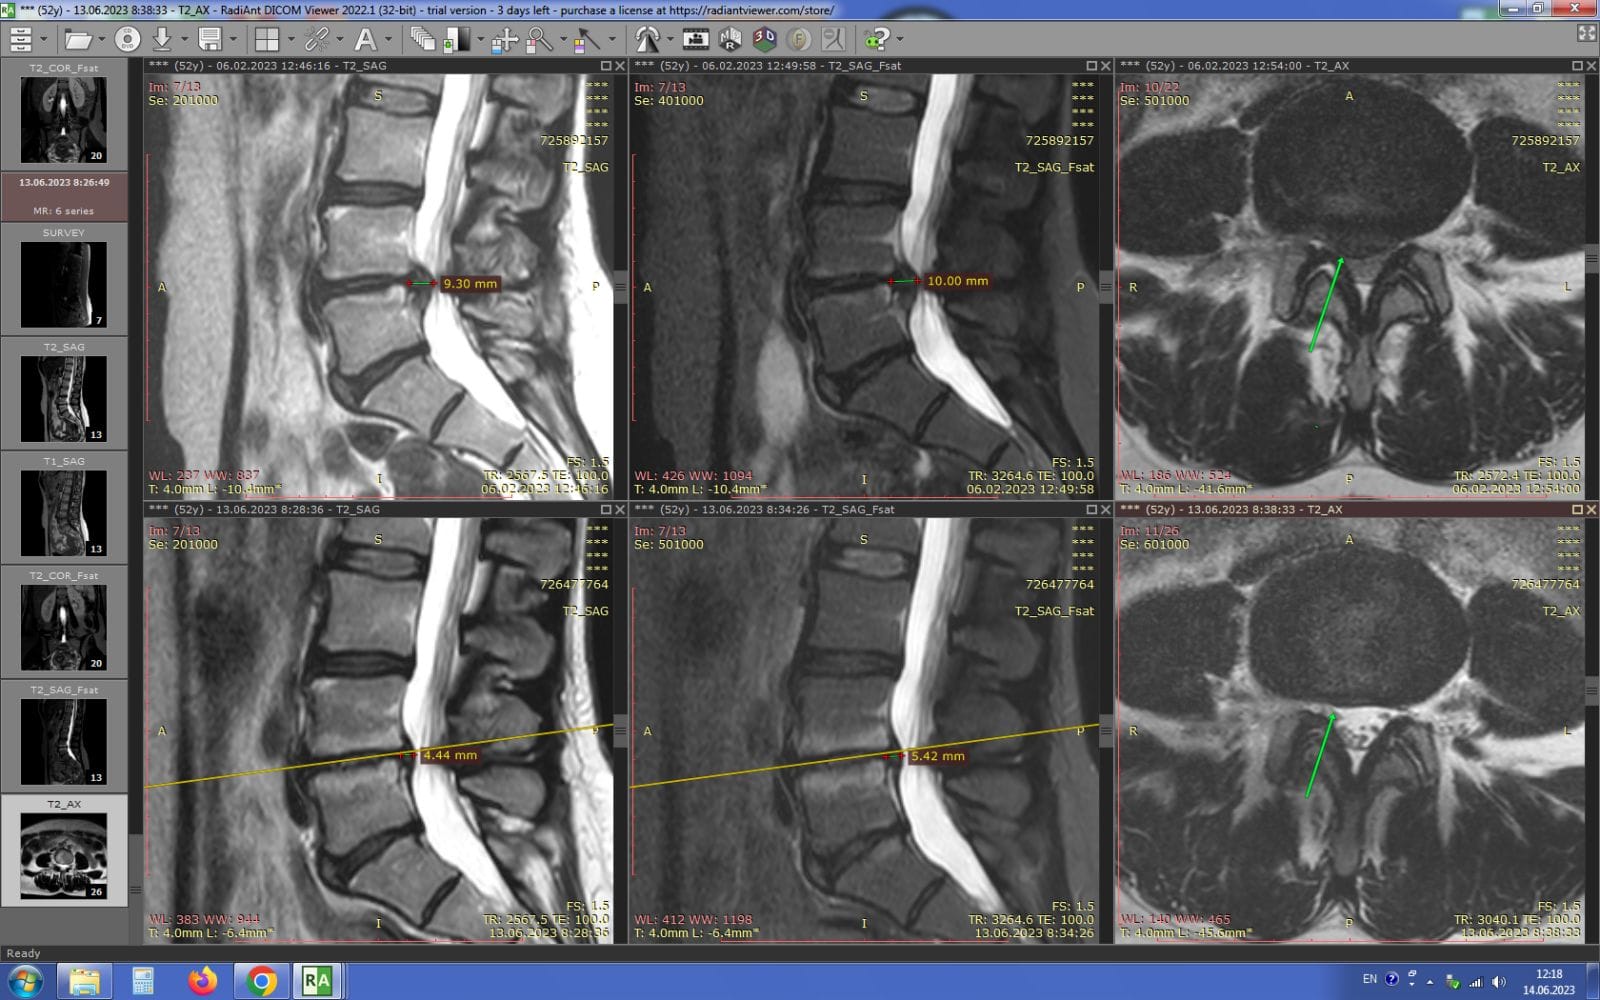

Метод лікування грижі шляхом стимуляції резорбції в Україні був впроваджений у 2020-2021 роках.  Алгоритм оцінки грижі на предмет резорбції, що використовується у клініках – є авторським, розроблений лікарем Боханом А.Ю.